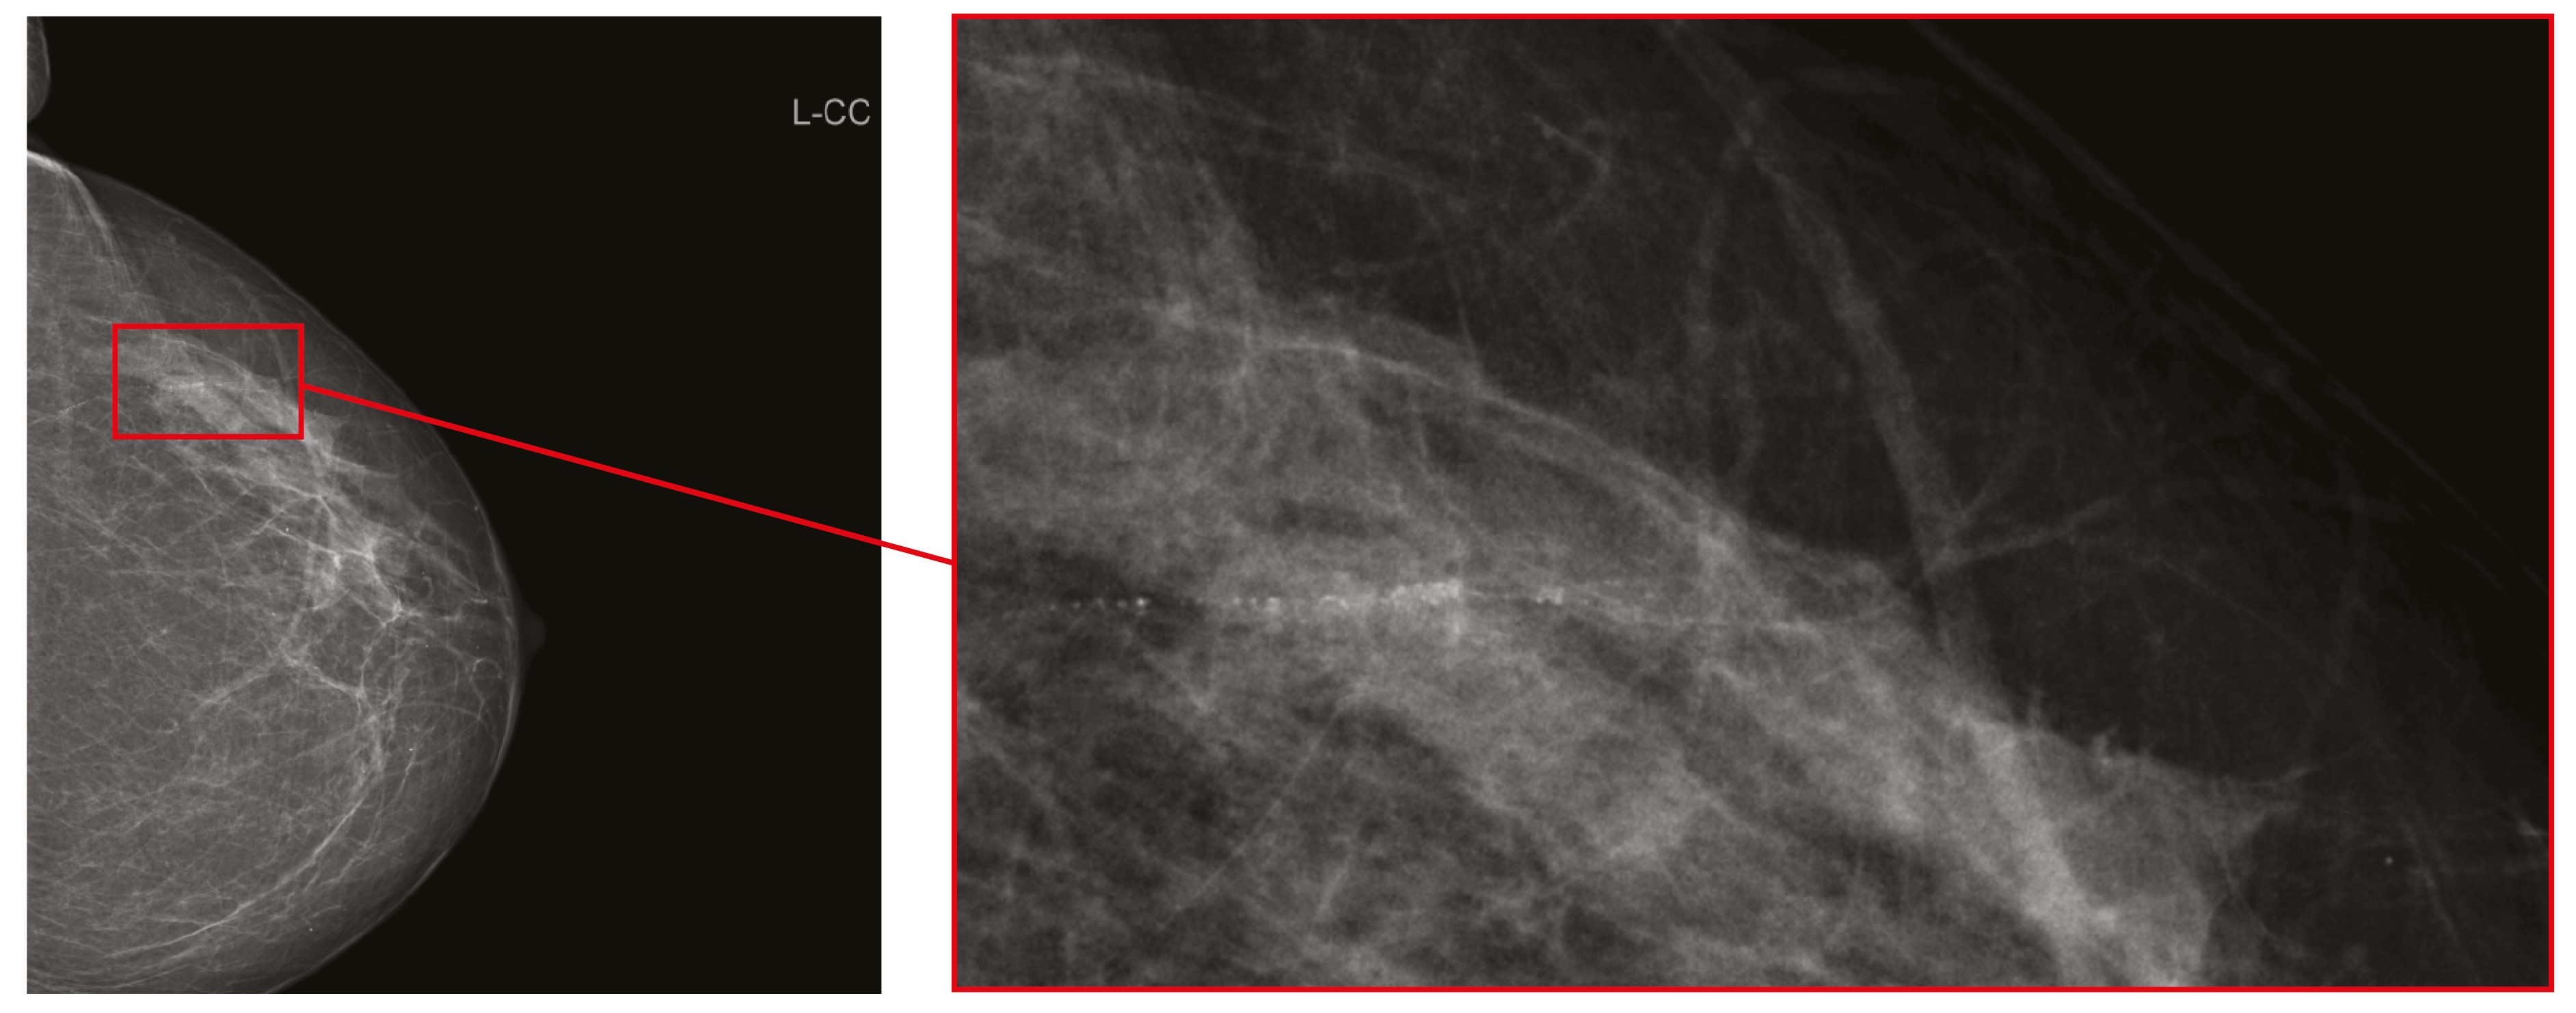

Однако присутствовали и единичные случаи значимого расхождения в оценках маммографических исследований. В одном из таких случаев рентгенолог, выполнивший первичное описание, и врачи, выполнившие пересмотр, обратили внимание на очаговое скопление микрокальцинатов в паренхиме правой молочной железы (рис. 1). Все врачи оценили изменения как соответствовавшие категории BI-RADS 4. Не исключено, что выявленная патология в правой молочной железе повлияла на оценку левой молочной железы у той же пациентки, где двое рентгенологов распознали в указанной на рис. 2 зоне интереса очаговое скопление микрокальцинатов и определили категорию BI-RADS 4, тогда как остальные врачи интерпретировали изменения как линейную фрагментарную кальцинацию в проекции стенки сосуда и установили категорию BI-RADS 2.

Рис. 2. Левая молочная железа в краниокаудальной проекции с выделенной областью интереса. Мнения рентгенологов разделились: в области интереса – очаговое скопление микрокальцинатов или линейная фрагментарная кальцинация в проекции стенки сосуда